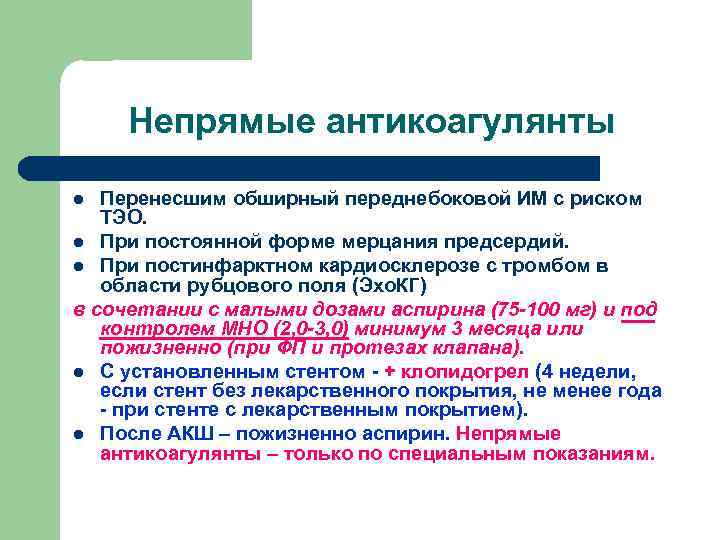

Непрямые антикоагулянты Перенесшим обширный переднебоковой ИМ с риском ТЭО. l При постоянной форме мерцания предсердий. l При постинфарктном кардиосклерозе с тромбом в области рубцового поля (Эхо. КГ) в сочетании с малыми дозами аспирина (75 -100 мг) и под контролем МНО (2, 0 -3, 0) минимум 3 месяца или пожизненно (при ФП и протезах клапана). l С установленным стентом - + клопидогрел (4 недели, если стент без лекарственного покрытия, не менее года - при стенте с лекарственным покрытием). l После АКШ – пожизненно аспирин. Непрямые антикоагулянты – только по специальным показаниям. l